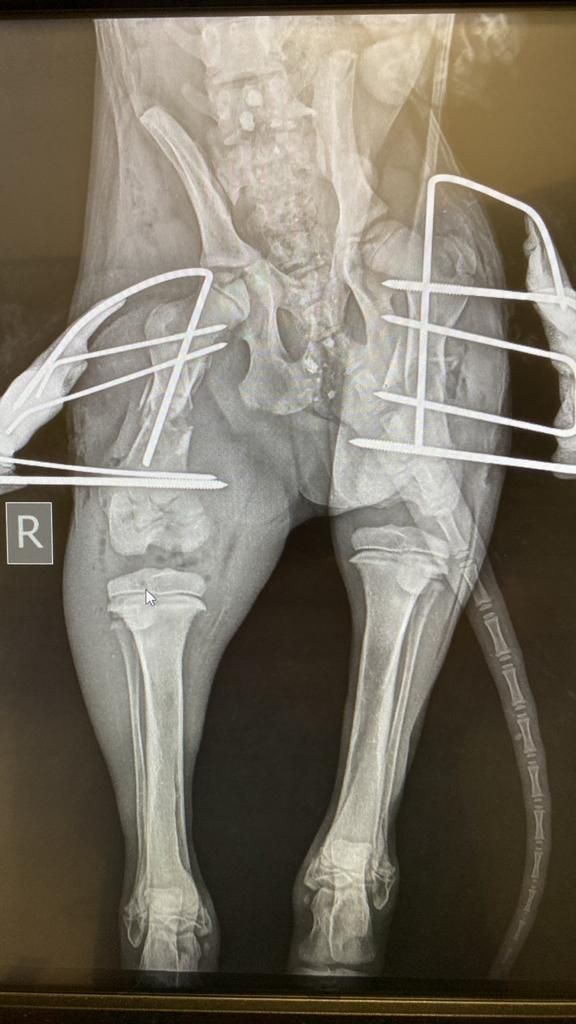

Erste Operation gelungen!

Am 16.11. ist Cosima Senta operiert worden, zuerst ist der linke Kopf des Hüftgelenksknochens entfernt bzw. Der Knochen gerichtet worden und so die Fehlstellung der Beine korrigiert worden. Beide Seiten sind leider betroffen, aber links musste zuerst behandelt werden. Zugleich wurden die Schwanzwirbel so gerichtet, dass der Knochenbau gerichtet ist, damit die Hündin einmal wieder korrekt und schmerzfrei laufen kann. Zugleich mussten die Milchdrüsen im betroffenen Bereich entfernt werden.

Diese erste Operation hat 600 € gekostet und wir danken von Herzen Lissy Schleich, die das Geld für Cosima Senta gespendet hat.

Der Tierarzt empfiehlt jetzt ein CT, um nach diesem ersten Schritt weiter planen zu können, welche Knochenschnitte und Stabilisierungen nötig sind, wie ein Neuaufbau im Beckenbereich durch Treiber gestützt sinnvoll ist. Allein für das CT müssen wir weitere 300 € stemmen, hinzukommen pro Seite 300 € für die Drei-D-Stabilisatoren/ die Treiber bzw 550 € für beide zusammen, wenn sie zeitgleich fixiert werden sollen, worüber die CT Aufnahme aufklären wird. Für uns bedeutet dies, wir sammeln weiter, damit Cosima Senta bald unbeschwert laufen und springen kann. Sie hat es wirklich verdient. Hilfe ist hier gefordert, diese knapp 900 € müssen wir erst einmal zusammenbringen. Jede Spende für die arme Maus hilft, sie hat doch noch ein ganzes Leben vor sich.